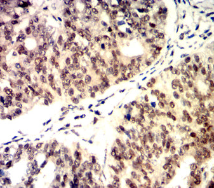

CDK4 Mouse Monoclonal antibody[4A11E]

Immunogen :   Purified recombinant fragment of human CDK4 (AA: 77-303) expressed in E. Coli.

IHC    1/200 - 1/1000